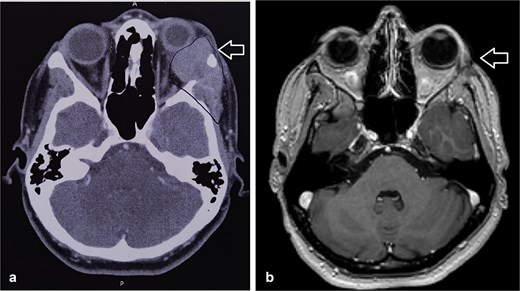

Histopathologic examination showed ACC displaying multiple cribriform structures composed of epithelial and basal/myoepithelial cells (Fig. 2). Molecular profiling indicated negative estrogen receptor, progesterone receptor, HER2, and PDL-1.

The tumor is composed of dual cell populations of basaloid epithelial cells and myoepithelial cells, arranged in characteristic cribriform and tubular growth patterns.